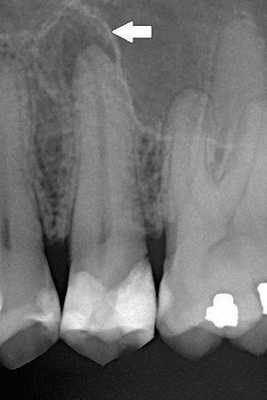

Дополнительные методы обследования: было проведено диагностическое рентгенологическое исследование. При анализе внутриротовой контактной рентгенограммы зуба 1.5 отмечался очаг разряжения костной ткани в области верхушки корня зуба 1.5 (рис. 2). Рис. 2. Внутриротовая контактная рентгенограмма зуба 1.5 до лечения. При проведении электроодонтометрии зуба 1.5 было получено значение более 100 мкА. При проведении термометрии зуб 1.5 не реагировал на холодовой и тепловой раздражители.

В результате проведения основных и дополнительных методов обследования был поставлен диагноз: хронический апикальный периодонтит зуба 1.5 (К04.5). Однако наличие внутренней корневой резорбции было выявлено только в процессе эндодонтического лечения зуба.